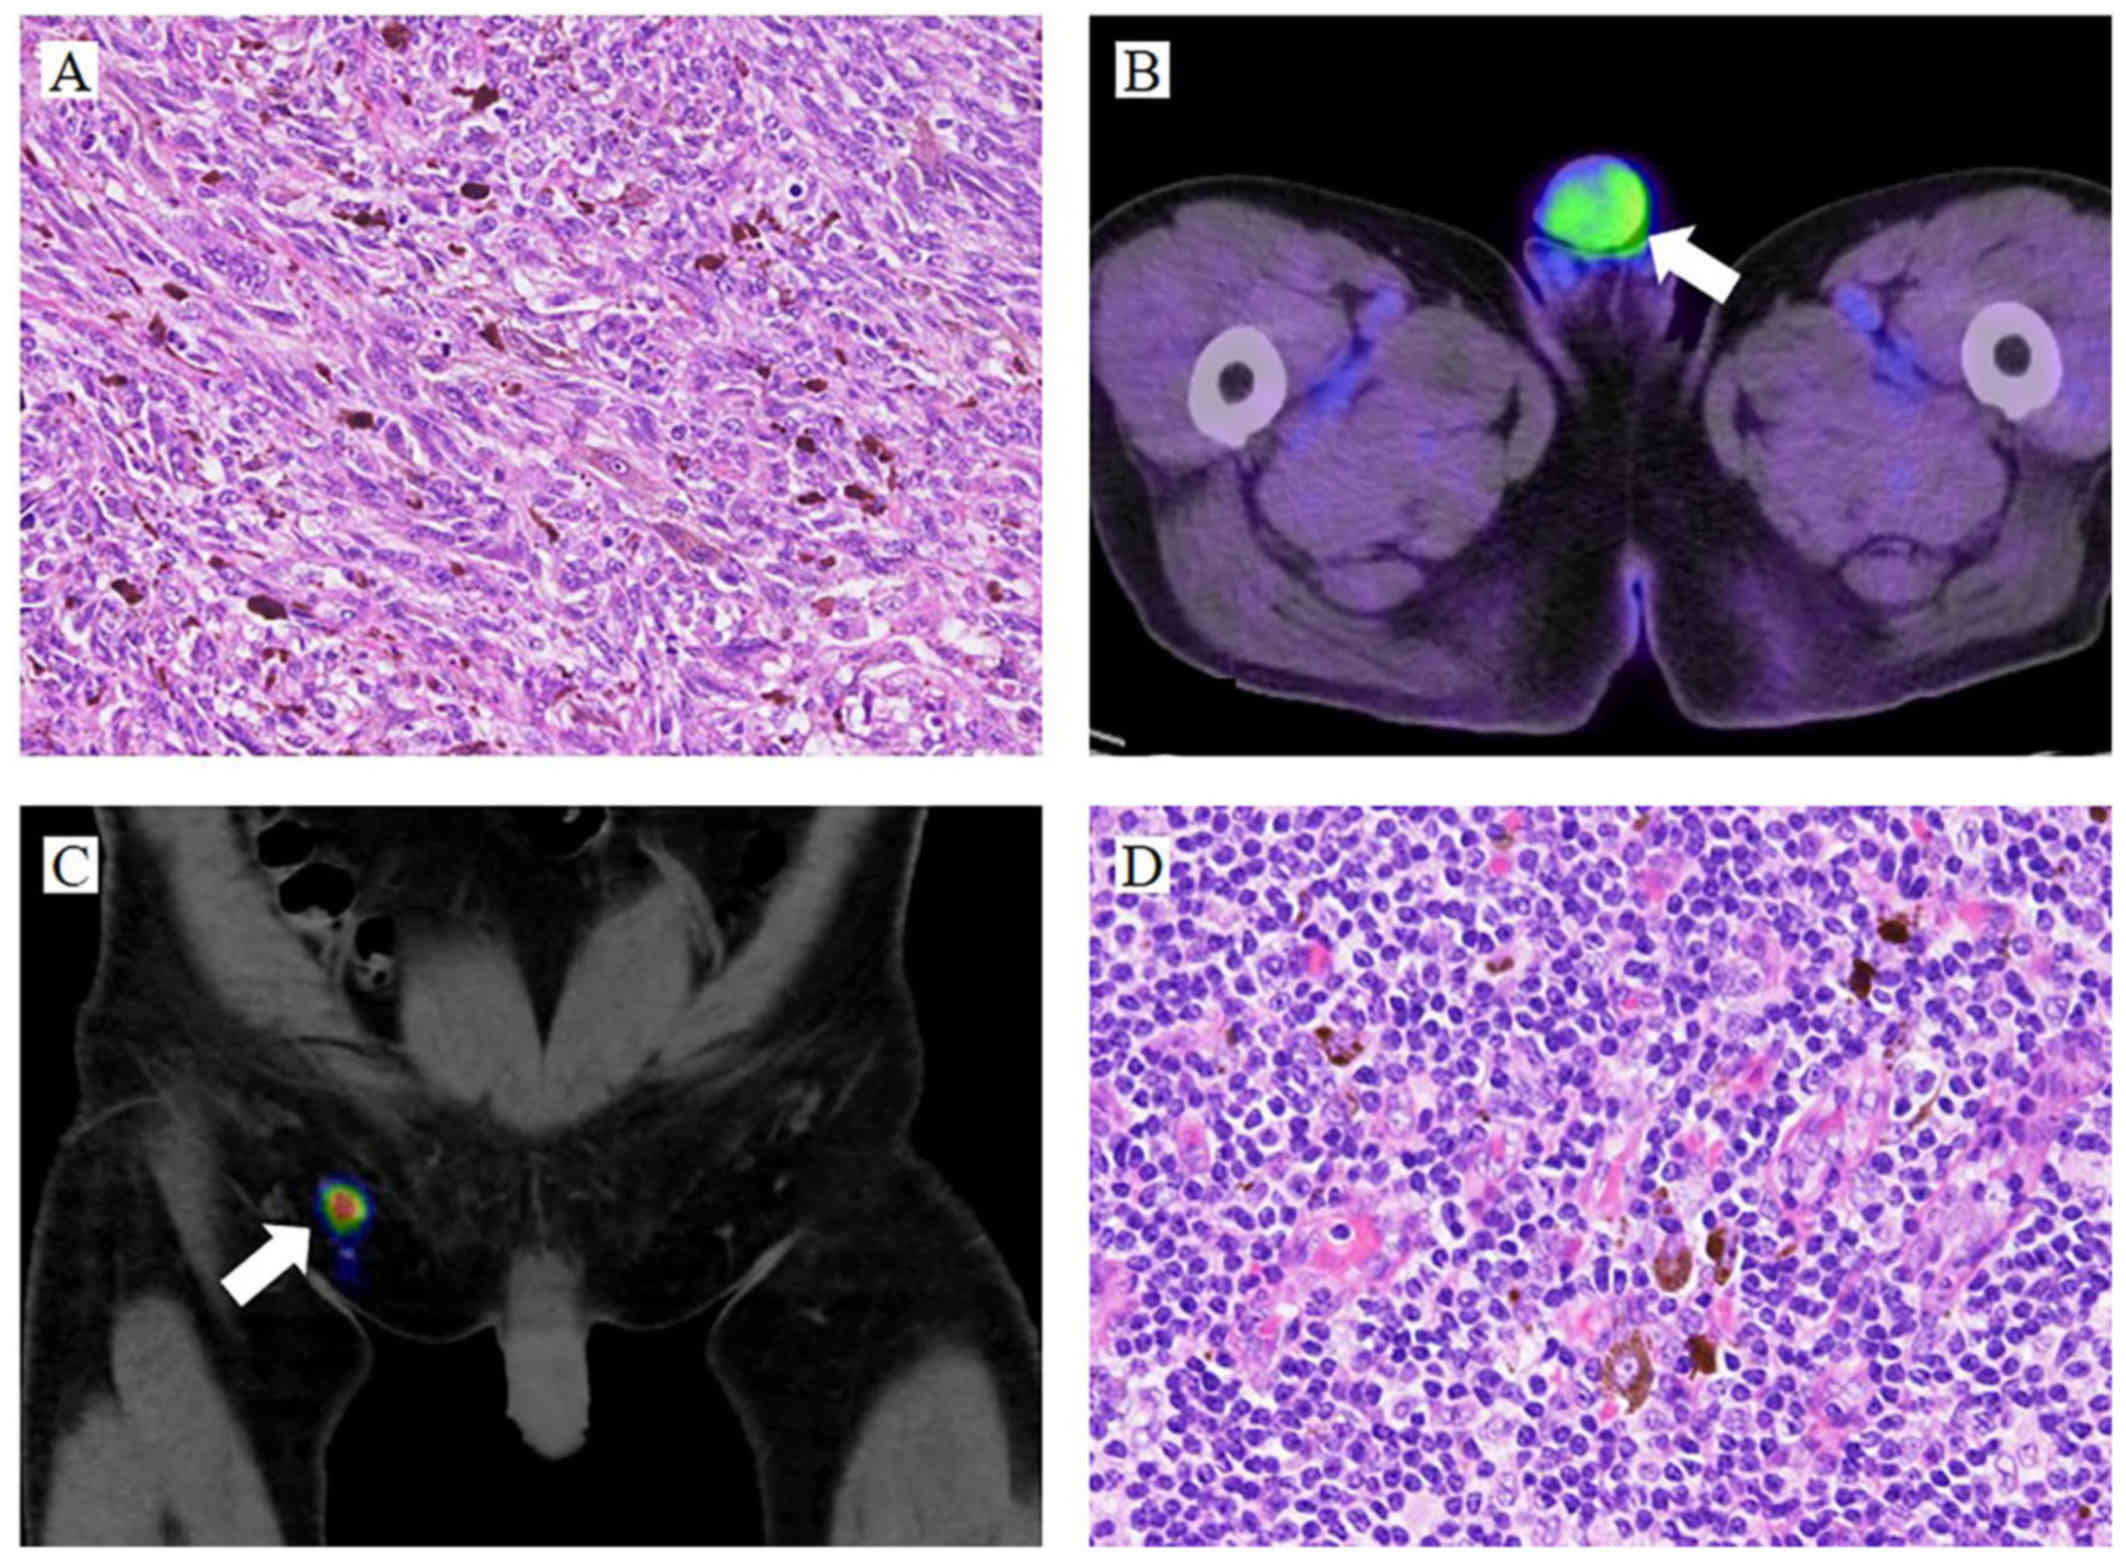

In contrast to penile melanosis, which is benign, penile melanoma is a form of skin cancer. Penile melanoma is rare, but it is crucial to differentiate between these two conditions. Unlike penile melanosis, penile melanoma is an aggressive disease that requires prompt diagnosis and treatment. Clinical features of melanoma include asymmetry, irregular borders, multifocality, variegated pigmentary patterns, and a large size. Moreover, swelling at the end of the penis, particularly when the foreskin is constricted, and lumps under the skin in the groin area can also be signs of penile cancer.

The prognosis for penile melanoma is often poor because it is usually diagnosed at an advanced stage. Primary penile melanomas are very rare, accounting for a small percentage of all melanomas. Penile mucosal melanoma can occur around the penis (glans, foreskin, shaft, meatus, or scrotum). It may manifest as a dark pigmented area with irregular borders. If you are concerned about a pigmented area on your penis, it is important to consult a doctor for a diagnosis.

Indeed, one of the major mimickers of mucosal melanoma, and thus of penile melanomas, is melanosis. Clinically, despite its benign behavior, melanosis can, at times, share features with malignant melanoma: asymmetry, irregular borders, multifocality, variegated pigmentary patterns and large size. Lumps under the skin in the groin area. If the cancer spreads from the penis, it most often travels first to lymph nodes in the groin. This can make those lymph nodes swell.

While penile melanoma is rare, it is crucial to differentiate between benign and. Some people also fear penile melanosis could lead to melanoma which is a very rare condition.